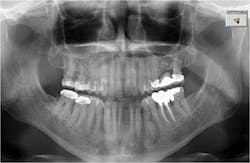

In the present case, a 61-year-old male was referred to my periodontal office by his general dentist for an evaluation of pain and bleeding to the lower right mandible. The patient’s medical history consisted of controlled type 2 (noninsulin dependent) diabetes and hypertension. Upon review of the panoramic radiograph (figure 1), the periodontal defects are not clearly evident, thus showing the importance of proper radiographs to detect periodontal defects. The periapical radiographs (figure 2) clearly show subgingival calculus, grade 1 furcation on No. 30, grade 3 furcation on No. 31, and an advanced intrabony defect on the distal of No. 30. Clinically, there was no mobility to either No. 30 or 31 and both teeth were vital. Tooth vitality is an extremely important diagnostic factor in treatment panning. Periodontal charting of the lower right was also performed, and the lower right exhibited bleeding and inflammation (figure 3).